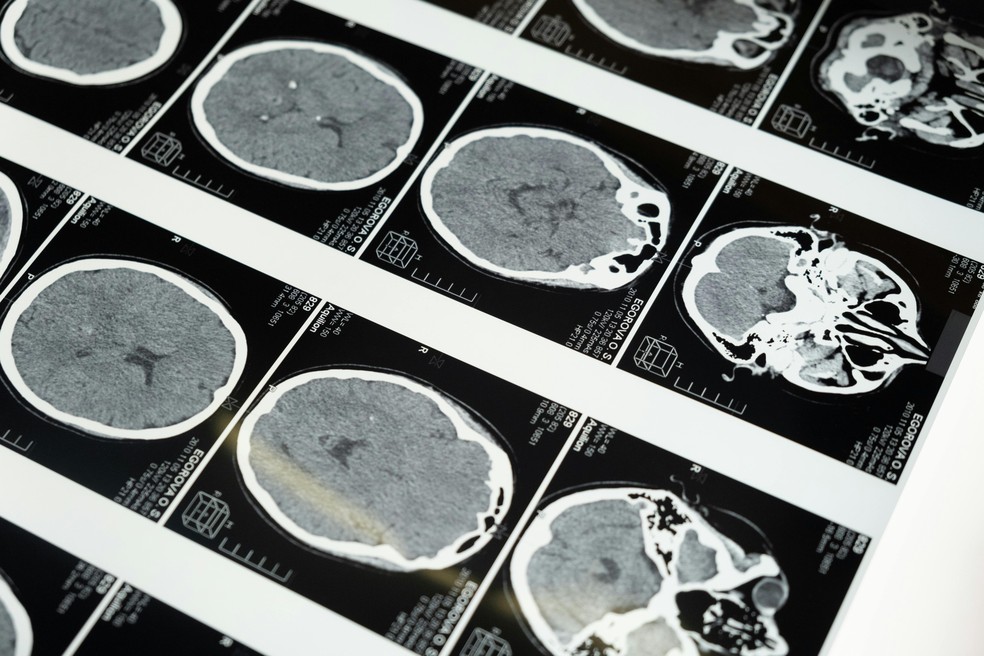

O estudo usou tomografias cerebrais por emissão de pósitrons (chamadas de PET) para investigar os níveis da enzima FAAH em 13 jovens adultos. Oito voluntários fumavam apenas cannabis, enquanto cinco também fumavam tabaco diariamente. Os resultados mostraram que os usuários de ambas as substâncias apresentavam níveis mais elevados de FAAH – enzima que decompõe a “molécula da felicidade”, a anandamida.

Exames de imagem mostraram níveis elevados de uma enzima que reduz a “molécula da felicidade”, a anandamida — Foto: Pexels A quantidade de cannabis consumida pelos participantes girava em torno de um grama por dia. Já o número de cigarros variava de um a doze. Não houve grupo de comparação com uso exclusivo de tabaco, o que leva os cientistas a considerarem a hipótese de que a nicotina, sozinha, possa ser responsável por parte das alterações. Ainda assim, os autores destacam que os dados sugerem que há algo mais em jogo quando as duas substâncias são usadas em conjunto.